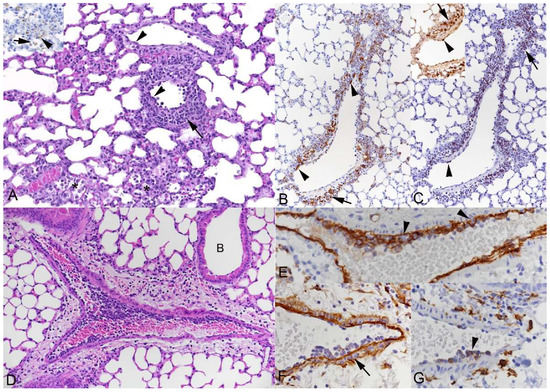

3.2. Respiratory Virus Infections, with Variable Degree of Alveolar Damage, and with or without Damage to Respiratory Epithelium, Elicit a Stereotypic Vascular Response

3.4. The Vascular Response after Respiratory Virus Infections Is Associated with Increased Expression of Adhesion Molecules in the Lungs